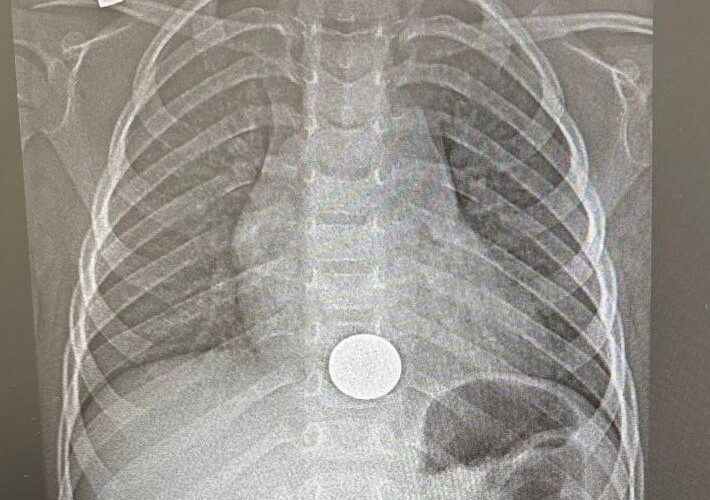

Ребенок поступил в больницу с жалобами на боли за грудиной. Как выяснилось, мальчик взял поиграть монету у старшего брата и случайно ее проглотил. О случившемся он сразу рассказал родителям. Мама оперативно доставила сына в медучреждение. После рентгенологического обследования опасения подтвердились: монетка была в пищеводе.

В итоге хирург эндоскопически удалил инородное тело. На это потребовалось около минуты. После процедуры малыша перевели в хирургическое отделение, а уже на следующий день, убедившись в его удовлетворительном состоянии, выписали домой.